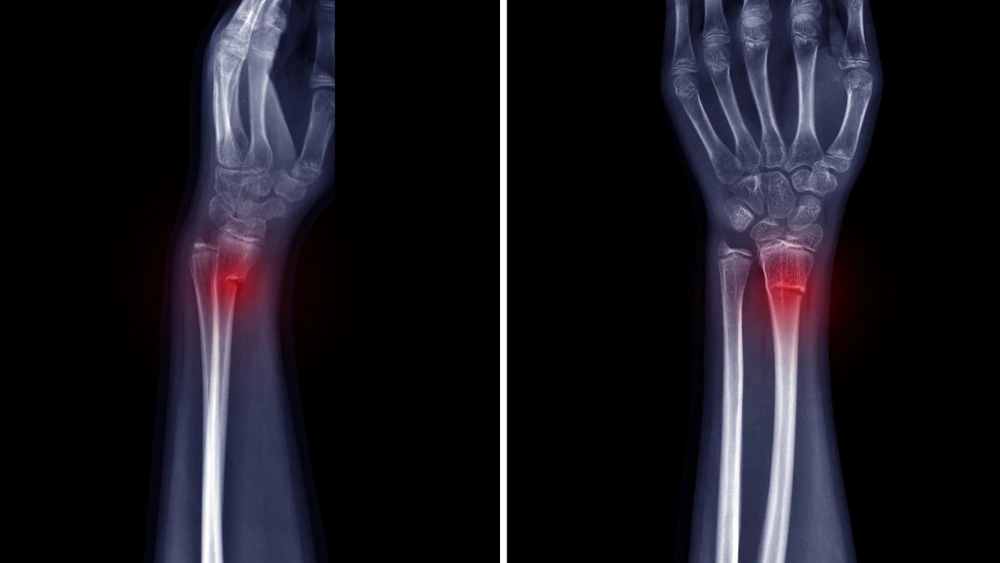

What is a Wrist Buckle Fracture?

In short, a wrist buckle fracture occurs when a small bone in the wrist bulges outside instead of breaking. But the long, detailed answer is that this is an injury that takes place when there is immense force put on the wrist. This powerful force leads to a small part of the wrist bones to bulge out instead of breaking. Now, this can happen when a child puts their hand out or extends it in front of himself / herself in order to break their fall.

Another thing to note is that these wrist buckle fractures can be tricky to identify even on an X-ray. Why is that? It’s because there is no break in the bone. The doctor will check the wrist and might even move / rotate it gently to locate the position of the pain.